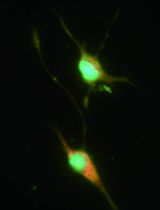

The islets of Langerhans are clusters of endocrine cells located within the pancreas. Insulin-producing beta cells are the major cell type within islets, with glucagon-producing alpha cells and somatostatin-producing delta cells the other major cell types. The beta cells are the target of immune-mediated destruction in type 1 diabetes (Graham et al., 2012). Failure of beta cell function accompanied by loss of beta cell mass is also a feature of type 2 diabetes (Wali et al., 2013). Therefore studying the biology of pancreatic islets is important to understand the pathogenesis of diabetes and to develop new therapies. Here we describe the isolation of mouse islets. This requires gentle enzymatic and mechanical digestion of the exocrine tissue and density gradient separation (Chong et al., 2004; Liu and Shapiro, 1995; Thomas et al., 1998). We then describe how islets can be cultured whole or dispersed into single cells for use in a variety of in vitro and in vivo analyses. Using this protocol reliably results in the isolation of 200-400 islets, depending on the strain of mouse.